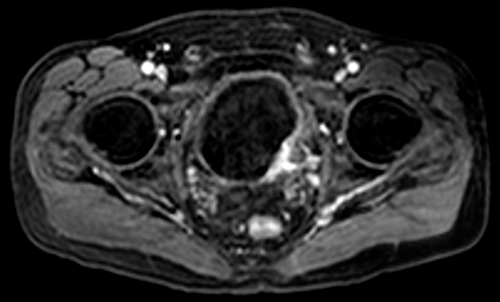

Figure 2. Axial T2 MRI showing a right sided tumour with the no evidence of extra-vesical extension.

T2 images should be obtained or reconstructed in three planes. T2 images allow assessment of the primary tumour and the bladder wall (Figure 2), and are superior to T1 images at assessing for invasion into adjacent organs such as the prostate or uterus. As well as axial imaging, a lateral bladder tumour or tumour at the dome is best assessed on coronal imaging, and an anterior tumour in the sagittal plane.

Figure 3a. DWI image in the same patient as Figure 2 shows the tumour to be high signal.

Figure 3b. ADC map shows restricted diffusion within the tumour.

Diffusion weighted imaging relies on proton diffusion properties in water. Diffusion images are obtained using multiple B-values, and the tumour will be high signal on the high B-value image and then show low signal on the corresponding apparent diffusion coefficient (ADC) map (Figure 3a and 3b). The ADC map reflects movement of water molecules and represents capillary perfusion and diffusion. Images are assessed in conjunction with the T2 images at the same level.

Figure 4. Early contrast enhanced images of the same patient as Figures 2

and 3 show avid enhancement of the internal half of the bladder wall.

If the tumour is seen to enhance, close evaluation is needed to assess if this is full thickness or less than half the thickness of the wall in order to provide radiological staging (Figure 4). The distal ureter may also be seen to enhance if the tumour is close to the ureteric orifice (Figure 5).